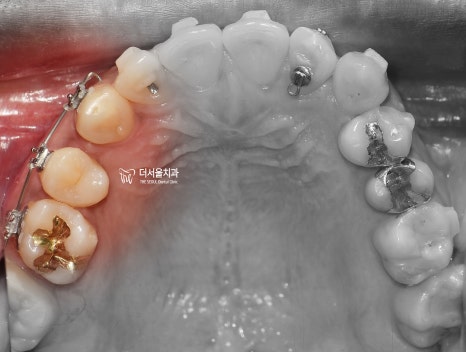

이건, 교합면에서 봤을 때

더 명확히 드러나게 됩니다.

상악 악궁에 배열 된 치아들은,

살짝 한쪽으로 쏠려 있는 것을 볼 수 있습니다.

어금니의 위치는 서로 대칭이 되는데,

앞니쪽으로 갈 수록 악궁의 형태가

조금 비대칭이 되는거죠.

그러면서 하악에서도,

치열의 불규칙성이 같이 관찰되는데